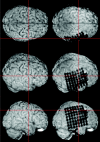

F<sc>ig</sc> 2.

Fig 2.

The resulting skull-stripped postimplantation image is visualized within MRIcro. A simultaneous examination of the skull-stripped preimplantation and postimplantation 3D MR images in two yoked MRIcro application windows gives an excellent overview of the exact location of each electrode contact. The viewer is able to grasp the electrodes’ spatial relation to the sulcal pattern of the brain and to anatomic landmarks (e.g., the central sulcus as pointed out here by the crosshairs).